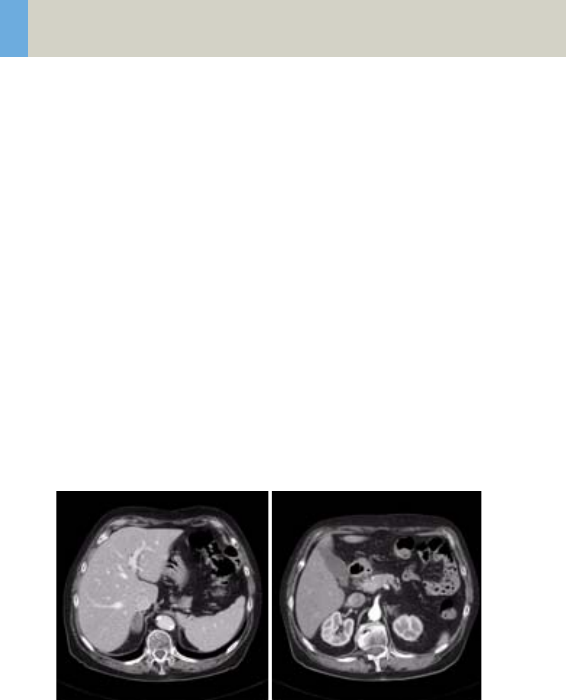

Abdomen 262

•Overview 262

- General Hints 264

- Body Kernels 265

•Scan Protocols 266